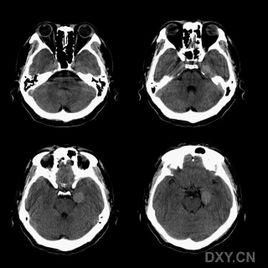

腦CT 2、腦CT可明確顯示顱內腫瘤的數目、部位、大小、輪廓、密度、瘤內出血、鈣化以及擴散程度。

3、腦CT對腦血管疾病診斷準確,並有助於確定治療方案。

4、腦CT對顱腦損傷可分辨血腫的大小、形態、範圍、數目及其鄰近腦組織壓迫情況。觀察有無亞急性或慢性顱內血腫的存在,判斷顱腦損傷的吸收、縮小情況,亦可顯示腦軟化、腦萎縮、腦積水及腦穿通畸形等後遺症。